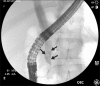

Cholestasis results from impairment in the excretion of bile, which may be due to mechanical obstruction of bile flow or impairment of excretion of bile components into the bile canaliculus. When present, cholestasis warrants prompt diagnosis and treatment. The differential diagnosis of cholestasis beyond the neonatal period is broad and includes congenital and acquired etiologies. It is imperative that the clinician differentiates between intrahepatic and extrahepatic origin of cholestasis. Treatment may be supportive or curative and depends on the etiology. Recent literature shows that optimal nutritional and medical support also plays an integral role in the management of pediatric patients with chronic cholestasis. This review will provide a broad overview of the pathophysiology, diagnostic approach, and management of cholestasis beyond the neonatal and infancy periods.